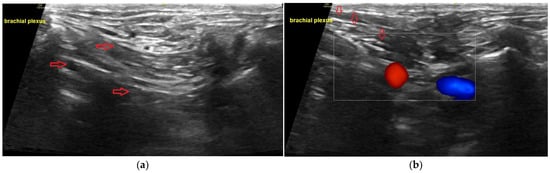

7.2. Brachial Plexus Block

- Campoy, L.; Bezuidenhout, A.J.; Gleed, R.D.; Martin-Flores, M.; Raw, R.M.; Santare, C.L.; Jay, A.R.; Wang, A.L. Ultrasound-guided approach for axillary brachial plexus, femoral nerve, and sciatic nerve blocks in dogs. Vet. Anaesth. Analg. 2010, 37, 144–153. [Google Scholar] [CrossRef]

- Akasaka, M.; Shimizu, M. Comparison of ultrasound-and electrostimulation-guided nerve blocks of brachial plexus in dogs. Vet. Anaesth. Analg. 2017, 44, 625–635. [Google Scholar] [CrossRef] [PubMed]